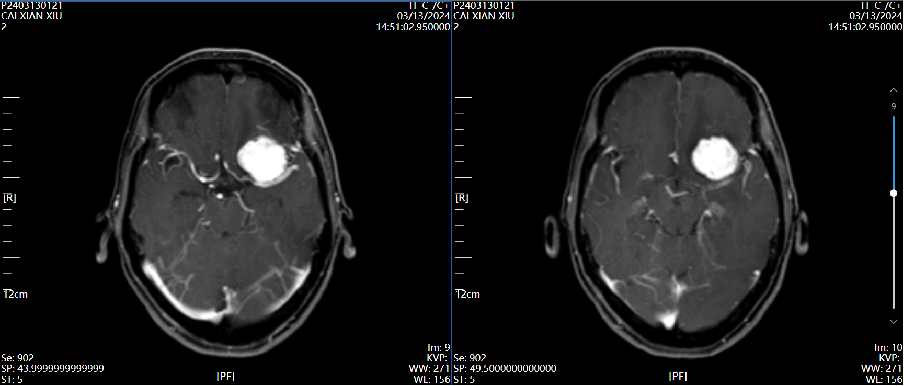

4、辅助检查:头颅磁共振检查提示:左侧前床突占位,约2.8×2.4×2.0cm大小,T1呈等低信号,T2呈等高信号,增强病灶明显强化,宽基底与前颅窝底、前床突相连,看见脑膜尾征。

磁共振增强 2024.03.13